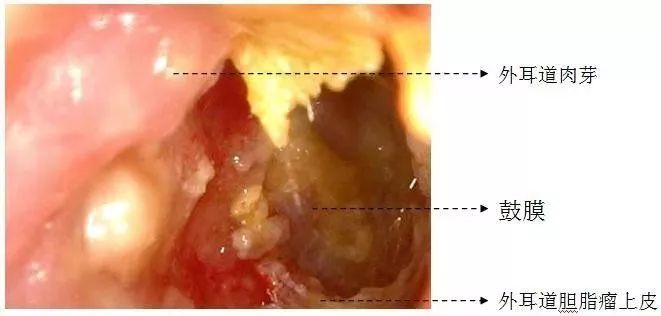

一位是杭州姑娘小林的经历,她因为耳屎总是掏不尽(并伴随着耳痛和听力下降)去医院看,结果被确诊为外耳道胆脂瘤(第一次听说)。胆脂瘤并不是真正的肿瘤,而是一种外耳道皮肤脱屑、胆固醇堆积、上皮包裹所形成的囊状团块,可通过手术去除。